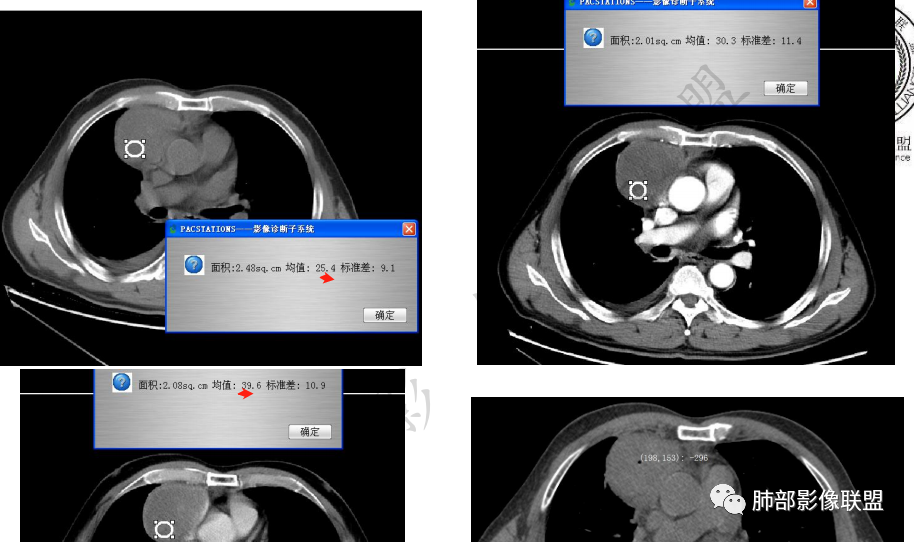

岁月:男性,68岁,右胸痛一天,无家族史,右上中叶纵膈旁占位;抽烟50年,3天1包。wbc高。与纵膈脂肪间隙不清,胸水,快进快出 分叶,有血管样强化,9.1-11.4-10.9。诊断:错构瘤,似乎都符合;但如果恶性放在前面,肉瘤、恶性。鉴别:错构瘤、侵袭性胸腺瘤;处理:经皮肺活检、手术。

必有路:老年人,右前纵隔占位,发病前纵隔脂肪干净,突发起病伴胸痛,白细胞增高病灶整体密度较为均匀,内有点状脂肪密度,位置个人觉得理胸腺区有点偏下,大部分囊性为主1、胸腺瘤伴突发梗死  突发起病,老年男,不支持点,位置偏下,囊变坏死太彻底,右侧胸廓内动脉没有增粗(实性肿瘤,往往会有间接供血增粗)倾向支持囊性病灶合并破溃感染2、囊性畸胎瘤伴破溃  影像上可以支持,脂肪含量比较少,发病年龄不太支持3、 皮样囊肿 可以有脂肪密度4、 支气管囊肿 理论上胸廓内都可以发生,肺内 后纵隔多见 张力大 圆5、心包囊肿  中纵隔更为多见综上,皮样囊肿>囊性畸胎瘤>胸腺瘤

周围脂肪间隙密度增高,内部小点状很低密度影

脂肪密度明显,还有钙化、囊性病变,支持含脂质类病变破裂

3.右上纵隔囊实性占位,边界清楚。中央见点状脂肪密度影,边缘见一点状钙化影,增强不均匀环形强化。